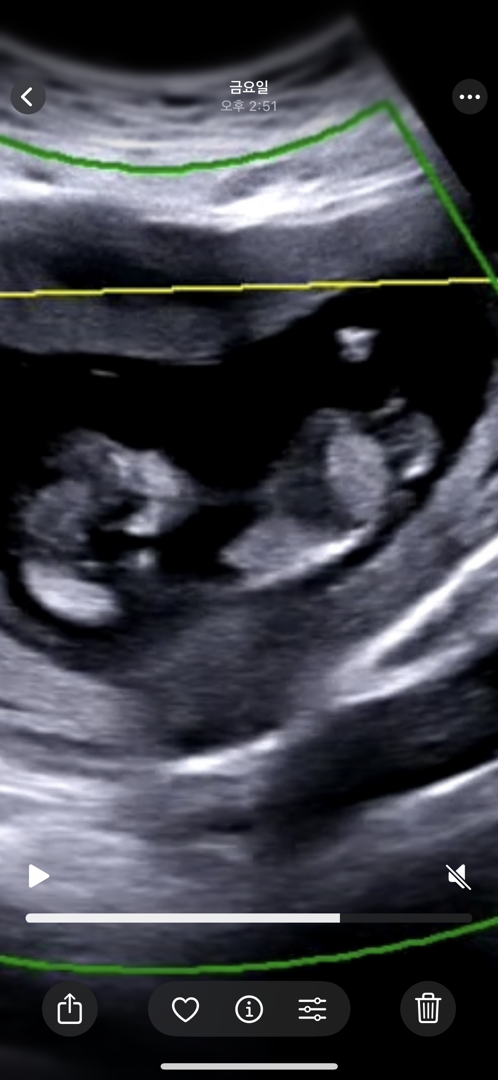

12주 각도법 잘 보시는분 !!! 셋째라 너무 궁금합니다 ㅠㅠ 부탁드려용

셋째라 너무 궁금하네요 ㅠㅠ 성별 마구마구 투표 부탁드립니다 🙏🏻🙏🏻